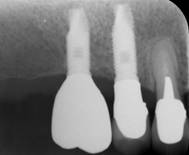

インプラント

インプラント埋入手術一本

22万円

インプラント上の冠や義歯も自費になります 。埋入後23か月程度で上物が入ります。

暫間インプラント

5万円

多数歯のインプラントのケースで、すぐに仮の歯を作りたいときに使用。インプラントが骨に結合すれば除去されます。

人工骨

3万円

上顎洞との間の骨が少ないとき、抜歯と同時にインプラントを埋入するときに必要になります。

ソケットリフト

5月万円(人工骨含む)

上顎洞との間の骨が少ないとき、上顎洞を押し上げ骨をつくります。

インプラント支台

7万円

プラチナゴールドのカスタム支台装置

インプラント上部構造(冠)

写真右端はジルコニア冠、中央は金属焼付けポーセレン冠。インプラント上部構造はネジの緩み、ネジの破折などに備えて取り外しできるセメントで付けています。中央に光って見える小突起は、取り外しの時引っ掛けるためのものです。インプラントは咬耗に伴う挺出がないので、ここ数年は

擦り減らないジルコニアを使っています。